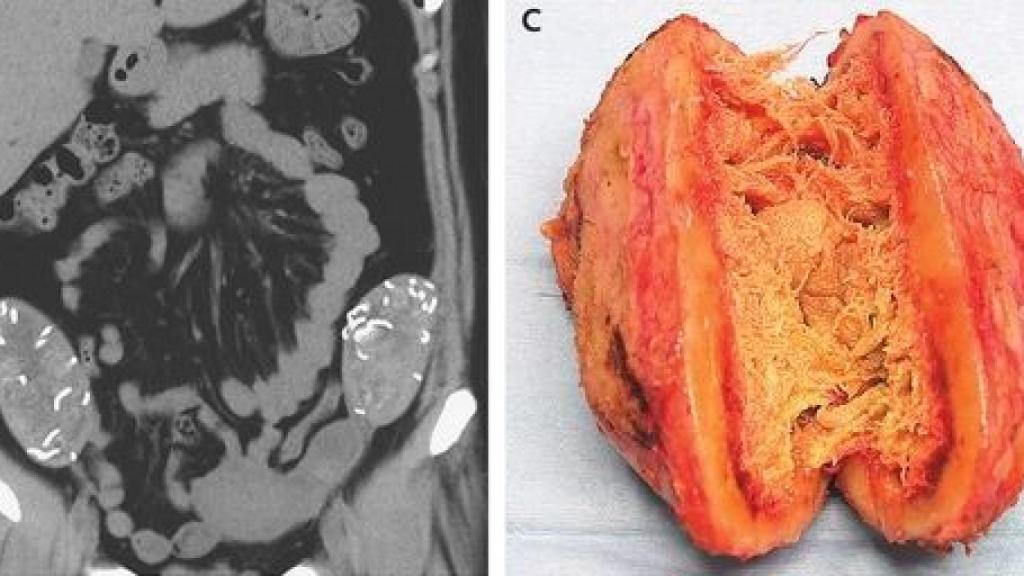

La imagen radiológica y una de las esponjas extraídas.

El informe de este caso, publicado recientemente en el New England Journal of Medicine, explica que los médicos tocaron ambas masas cerca de los huesos de la cadera derecha e izquierda de la mujer, una a cada lado. Posteriormente, con el objetivo de vislumbrar a qué se enfrentaban, le realizaron una tomografía computerizada del abdomen, la cual reveló que existían dos estructuras "fibrosas e hiperdensas". La mujer necesitaba pasar por una intervención quirúrgica para retirar esos cuerpos extraños de su pelvis.

Durante la operación, los cirujanos detectaron que las masas vistas en la prueba de imagen TC se encontraban en unas localizaciones entre el colon y la pared abdominal. Tras retirarlas y abrirlas, descubrieron que se trataba de esponjas de gasas quirúrgicas mezcladas con gruesas paredes de tejido fibroso o cicatricial. En otras palabras, se trataba de grupos de gasas que el mismo organismo había cubierto con el objetivo de protegerse de ambos cuerpos extraños.